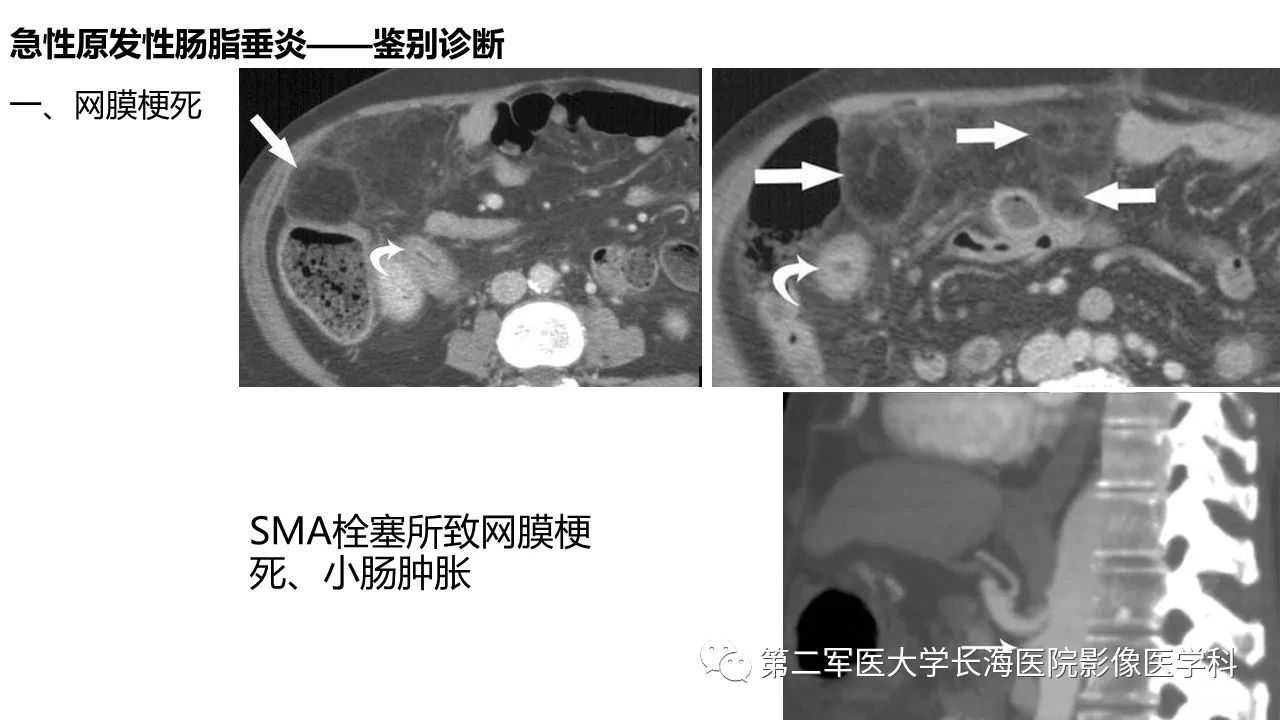

[腹盆] 急性原发性肠脂垂炎CT诊断与鉴别诊断

急性原发性肠脂垂炎CT诊断与鉴别诊断。

急性原发性肠脂垂炎CT诊断与鉴别诊断

来源:第二军医大学长海医院影像医学科